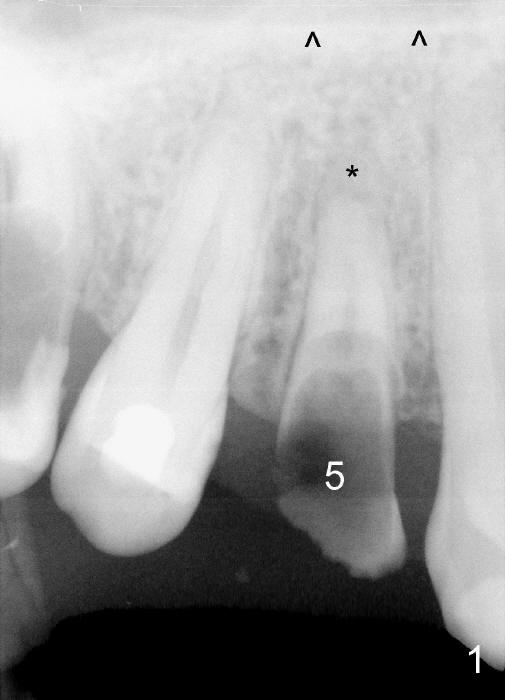

A 25-year-old black man has poor dentition. The tooth #5 is non-salvageable (Fig.1-6). Although the 1st bicuspids belong to the posterior teeth, anterior sensor holders should be used to show the sinus floor (Fig.1,2: ^). In contrast, PAs in Fig.3,6 (trimmed mesiodistally) are taken with posterior sensor holders; the sinus floor is out of view.

A long implant will be placed (possible 4.5x20 mm, Fig.2). A typical 1st bicuspid has 2 canals. In this case, there are most likely two roots (Fig.3): buccal (Fig.4 green dashed line) and lingual (Fig.5 pink dashed line).

It is reasonable to assume that the roots of the tooth #5 are bifurcated. If it is confirmed after extraction, a D implant may be more appropriate for this case (1, 2, 3).